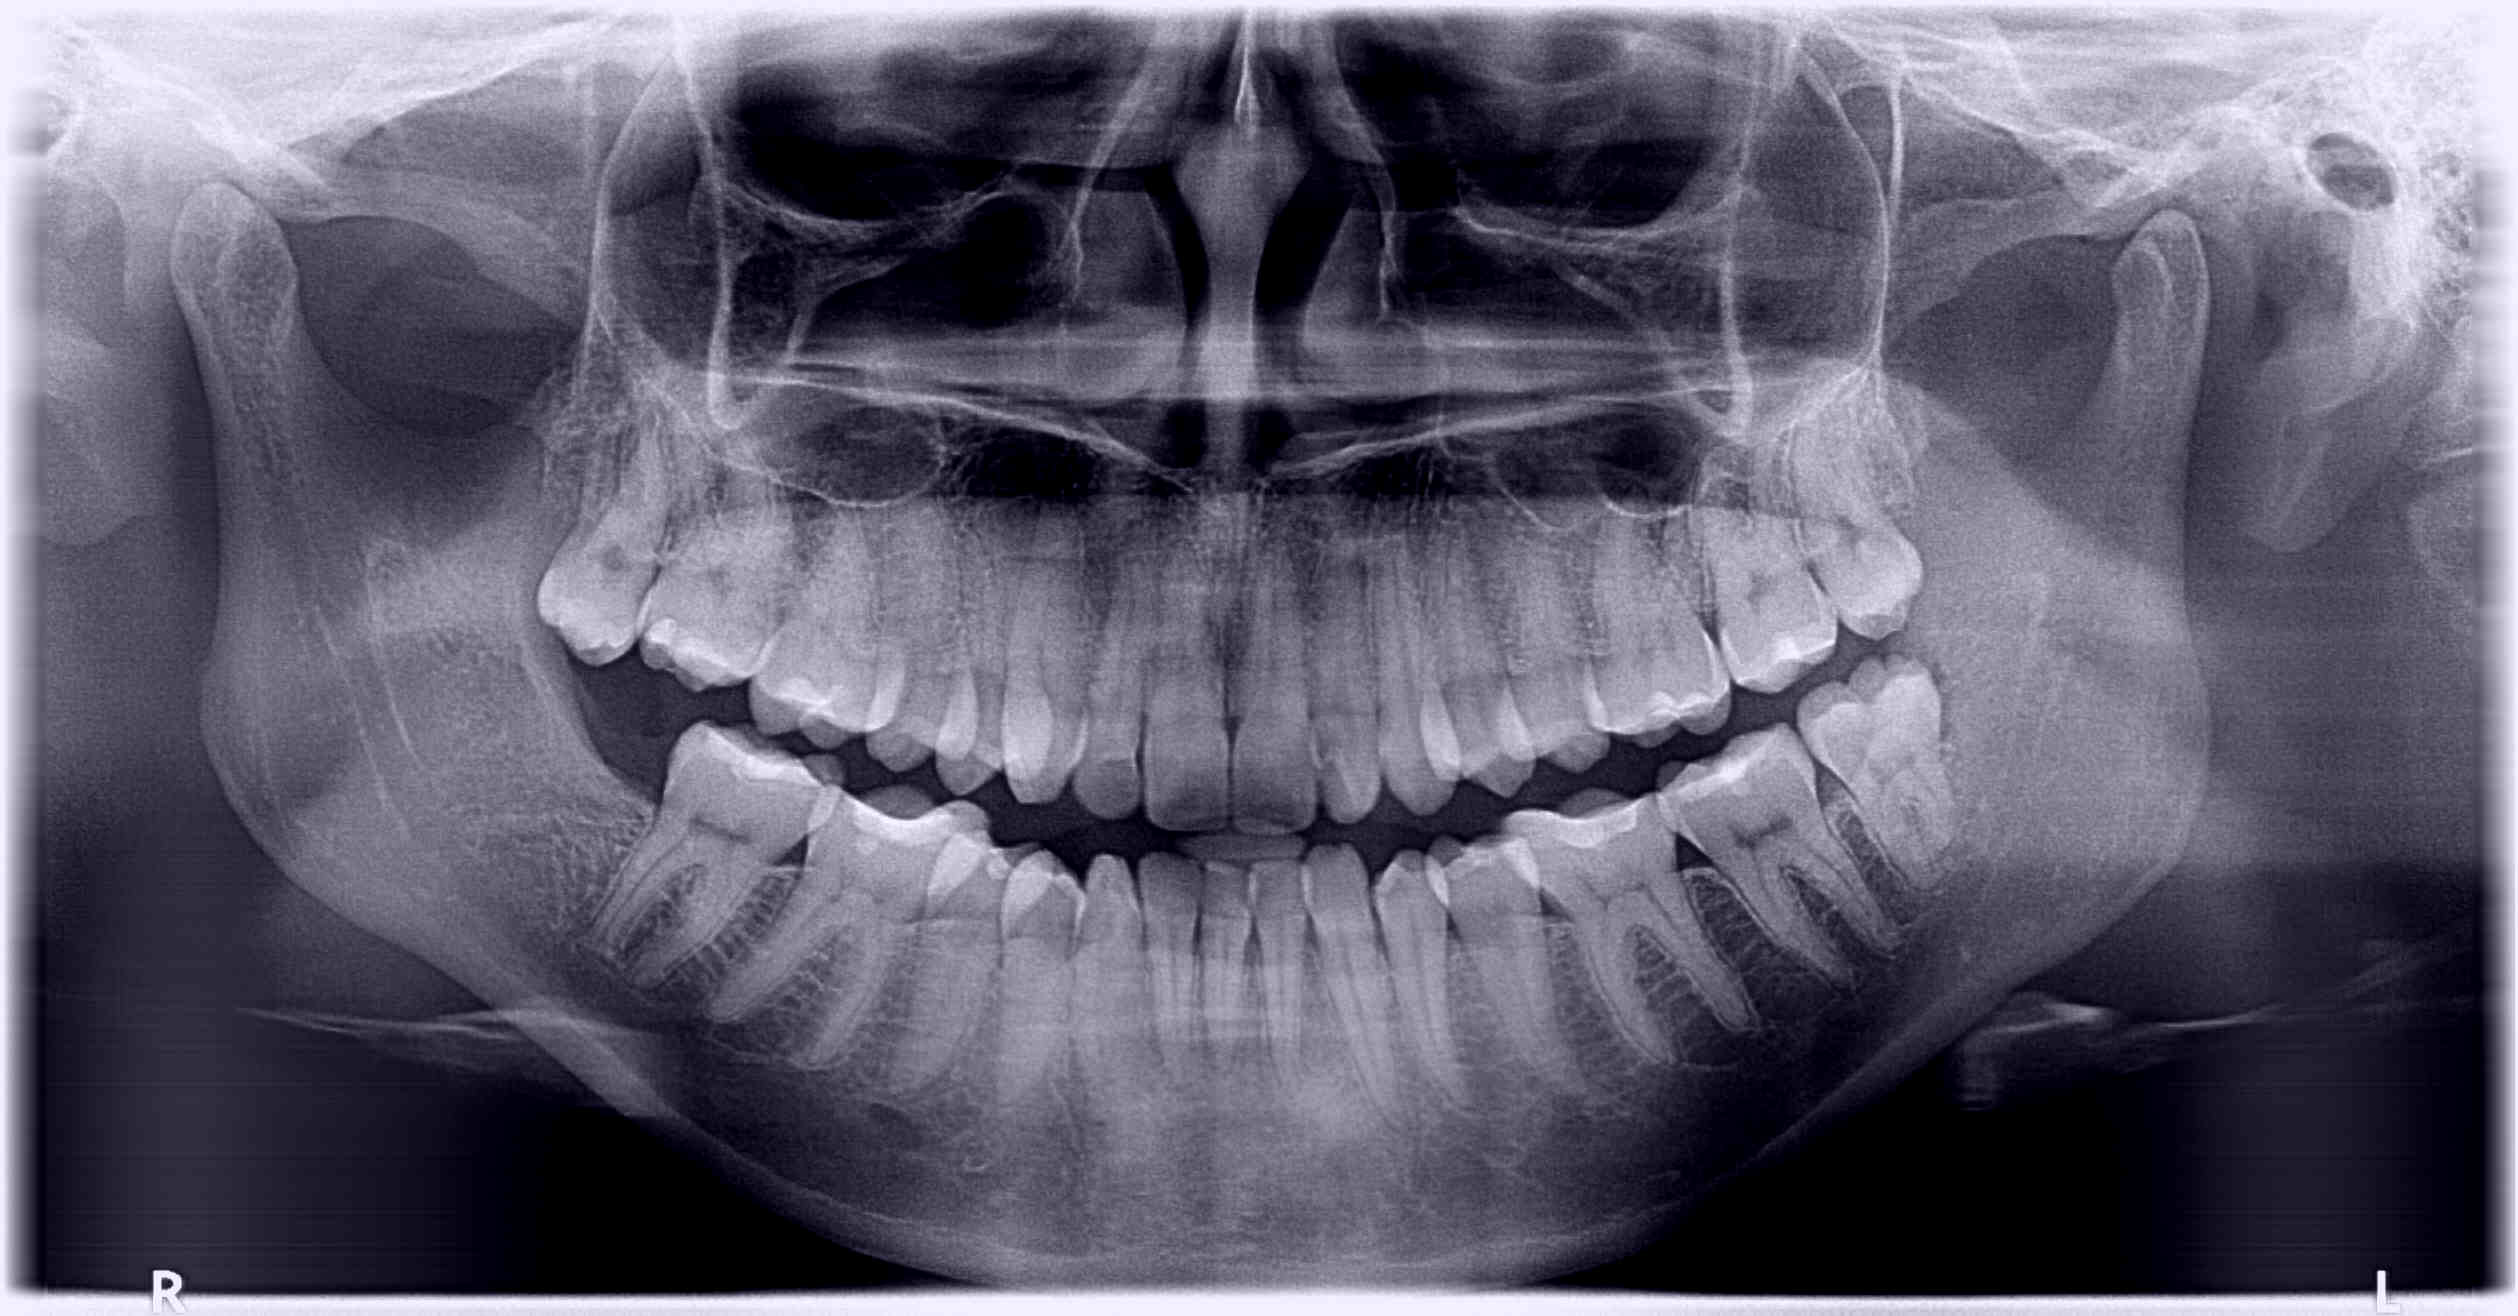

Digital opg available in Rohini Digital Xray in Delhi Digital O.P.G in Rohini OPG stands for Orthopantomogram, which is a type of dental X-ray that provides a panoramic view of the jaw and teeth. It's also known as a Panorex or Orthopantomagraph.